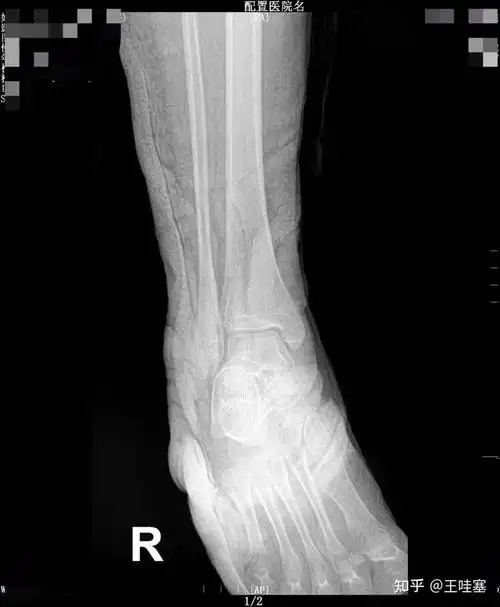

轻微骨裂拍的x片 看不懂 请问已经好了吗?